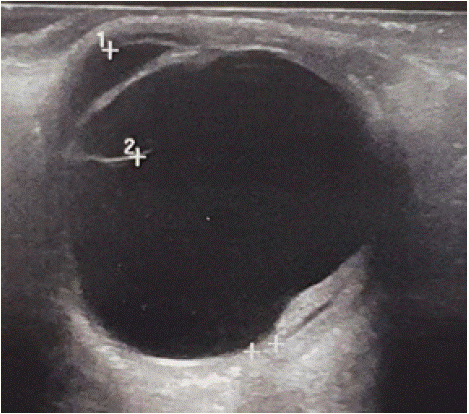

In the left eye, the findings on OCT angiography were obscured by hemorrhage and did not allow clear CNV demonstration. The spectral domain OCT (SD-OCT) of the right eye did show juxtafoveal CNV with associated subretinal fluid and hyperreflective dots (Figure 4). B-wave echo of the left eye shows extensive subretinal hemorrhage (Figure 5)

Figure 5: B-wave echo of the left eye shows extensive subretinal

hemorrhage.